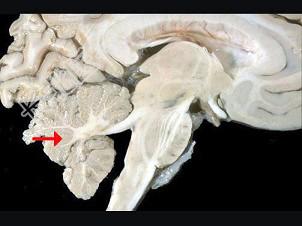

- 单项选择题如图箭头所示为颅脑哪个部位 ( )

A、顶叶

B、枕叶

C、小脑

D、脑干

E、额叶